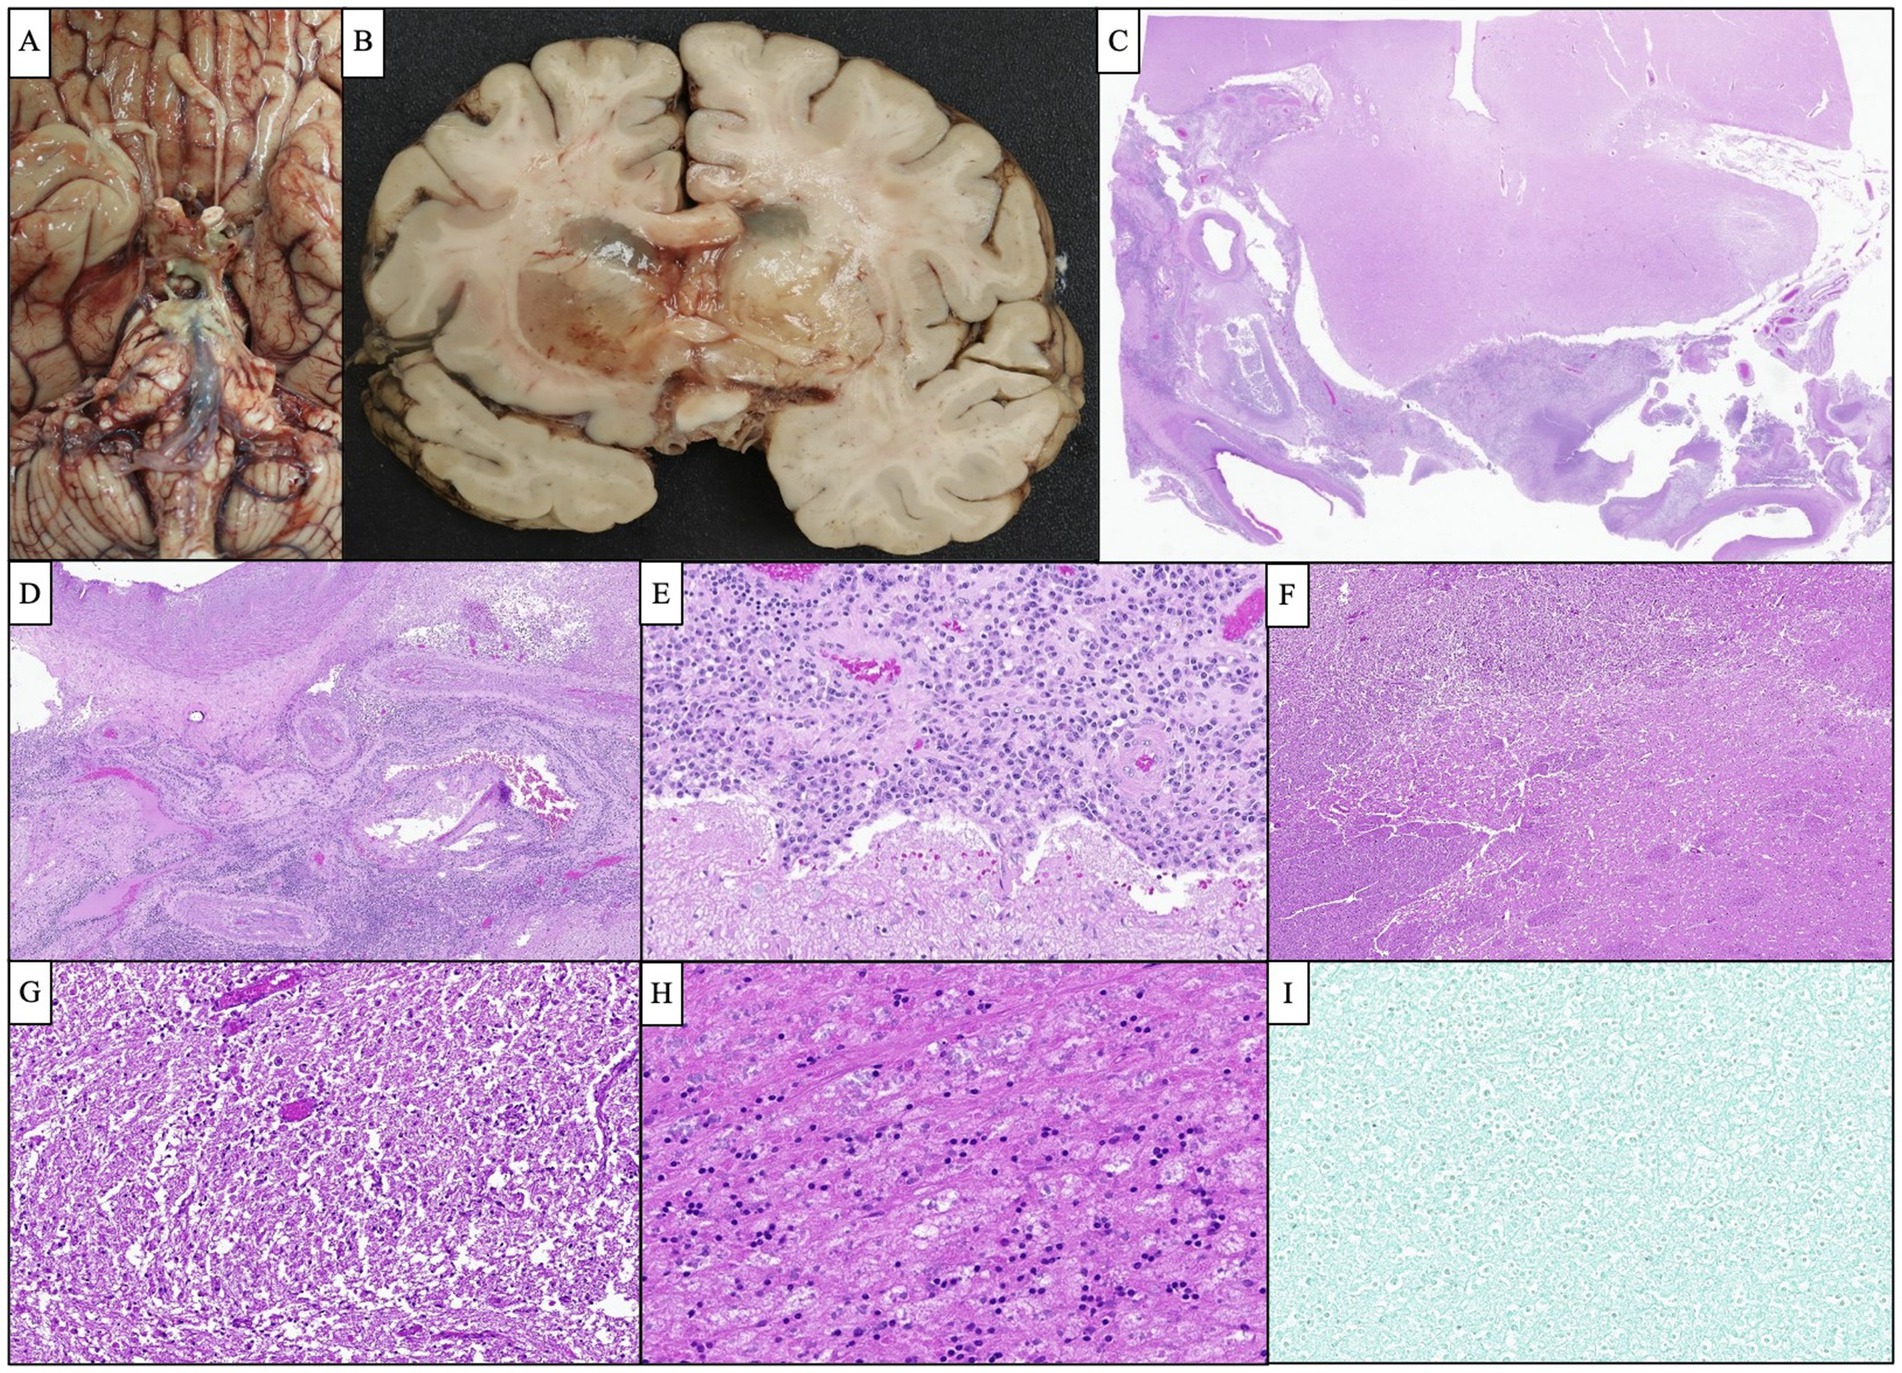

Given the patient’s worsening clinical symptoms and negative microbiologic workup, a serologic NGS test (Karius Test) was performed, which returned positive for Actinomyces israelii at 61 DNA molecules per microliter (MPM) and human herpesvirus 7 (HHV7) at 30 DNA MPM. The pathogenicity of Actinomyces was undetermined, while HHV7 was thought to be incidental. To confirm clinical significance, a transsphenoidal skull base incision and drainage were performed, revealing a necrotic-appearing pituitary gland and readily expressed purulent fluid. Pathological examination showed sulfur granule-like aggregates of branching filamentous bacteria consistent with Actinomyces (Figure 4). Targeted tissue NGS (Broad-Range PCR) also revealed trace Actinomyces israelii, further confirming the diagnosis of CNS actinomycosis. Broad-spectrum antibiotics were narrowed to IV ceftriaxone. Antibiotics were not further narrowed due to the presence of Gram-indeterminate cocci, which were suspected to represent either a secondary bacterial infection or dysmorphic actinomyces. Given the extensive infarcts involving the basal ganglia, thalami, brainstem, and cortices, the family elected to pursue comfort measures. The patient expired shortly after compassionate extubation, approximately 9 days after the suspected diagnosis of CNS actinomycosis. The autopsy revealed diffuse edema and purulence at the skull base, with areas of necrosis and inflammation extending to the walls of the large-caliber vessels. There were regions showing signs of subacute infarcts and meningitis as well. The cause of death was determined to be brain abscess formation with subsequent acute and chronic meningitis (Figure 5). A timeline of the patient’s disease course is provided in Figure 6.

Figure 5. Representative images of the autopsy findings. (A) Gross photograph of the brain’s base demonstrated a purulent fluid extending from the optic chiasm inferiorly along the brainstem down to the pons. (B) Bilateral basal ganglia showed severe edema and softening and were focally filled with gelatinous material causing marked compression of the adjacent ventricles. (C) Microscopic examination of the cavernous sinus revealed dense inflammation and focal abscess formation. (D) The inflammatory process extended to the wall of the large caliber vessels. Several smaller vessels appeared occluded with recanalization of the lumen. (E) Cavernous sinus inflammation extended to the leptomeninges causing severe meningitis. (F,G) Low and high-magnification images of the basal ganglia show severe edema and numerous macrophages consistent with subacute infarction. (H) The pituitary gland showed extensive necrosis with focal chronic inflammation. (I) GMS silver stain performed on multiple sections was negative for organism growth.